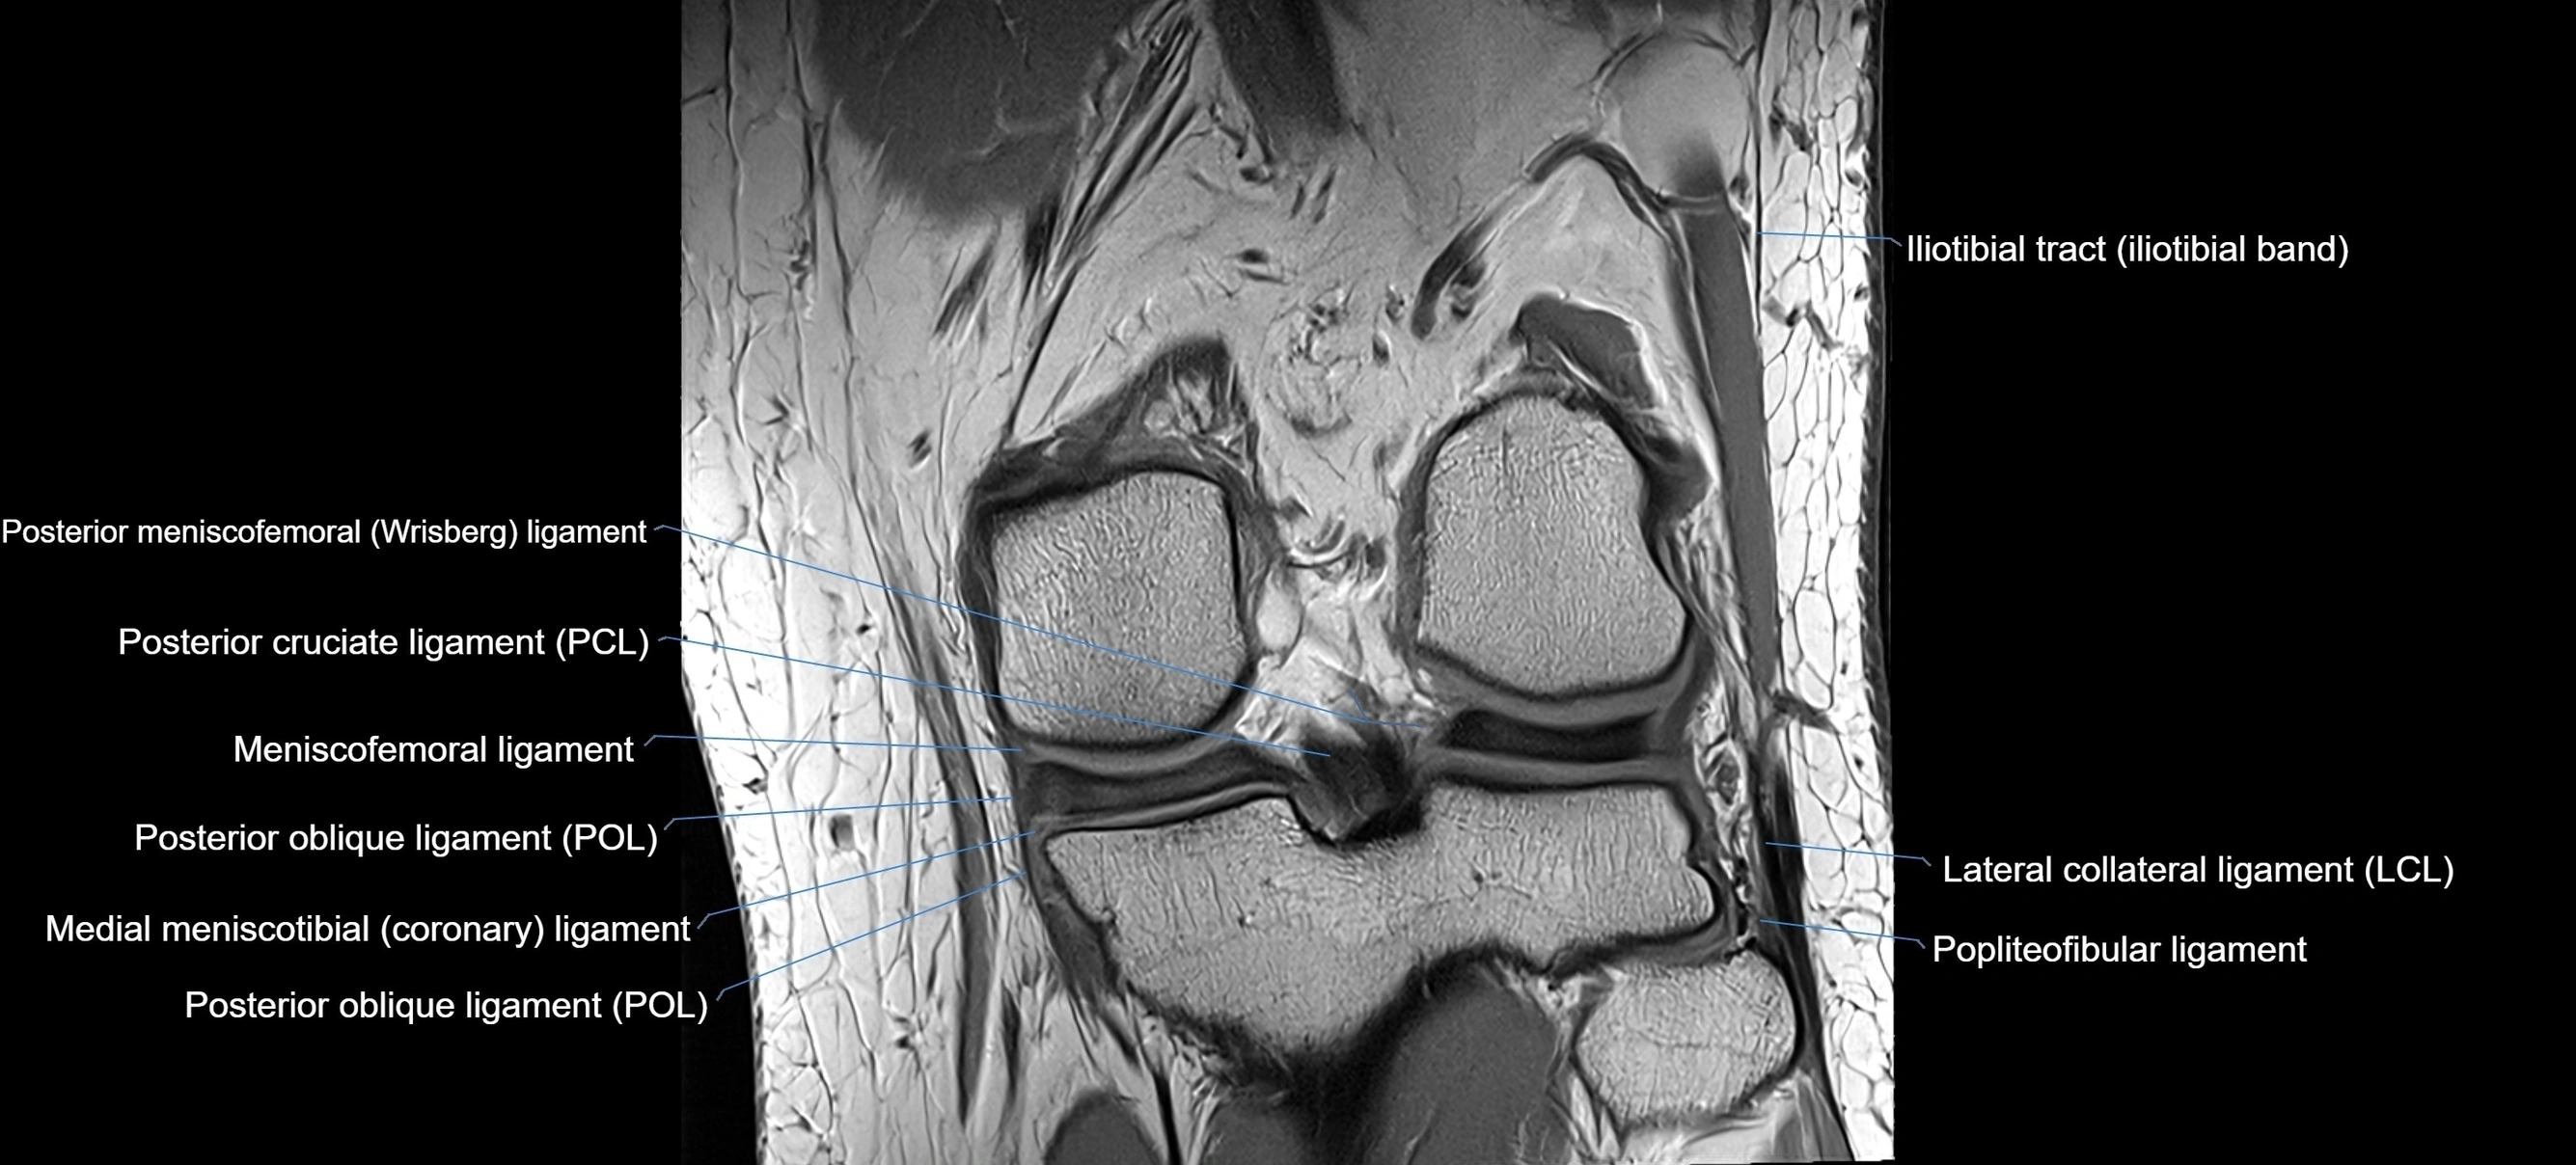

MRI images

image